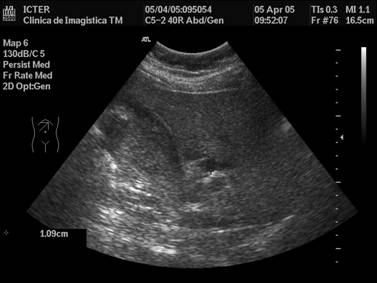

Icter mecanic

In cazul dilatarii marcate a CBP, calibrul acesteia tinde sa egaleze sau chiar poate depasi calibrul venei porte. Imaginea este caracteristica si este comparata cu cea a unei pusti de vanatoare cu doua tevi suprapuse. In acelasi timp, CBP poate prezenta tortuozitati accentuate.

In sectiuni transversale, segmentul distal dilatat al CBP poate imita o formatiune chistica pancreatica cefalica. Afirmarea dilatarii CBP intampina unele dificultati cand cresterea calibrului este minima sau tranzitorie si in anumite conditii particulare (la varstnic, postcolecistectomie).

Se pare ca cea mai inalta semnificatie pentru afirmarea dilatarii o are comportarea calibrului CHC, masurat proximal fata de incrucisarea cu artera hepatica, in segmentul sau situat anterior ramurii drepte a venei porte. Limita superioara a normalului fiind stabilita la 4 mm, valori egale sau de peste 5 mm sunt considerate net patologice.

In ceea ce priveste coledocul, opiniile sunt diferite, in functie de nivelul la care acesta a fost masurat, varsta pacientilor si evolutia sa naturala postcolecistectomie. Astfel, la pacientii necolecistectomizati, aprecierea limitei superioare a normalului variaza de la autor la autor, fiind citate valori de 6 - 8 mm. In general, insa, daca masuratorile se efectueaza in segmentul proximal al coledocului, o limita superioara de 6 - 7 mm poate fi considerata rationala.